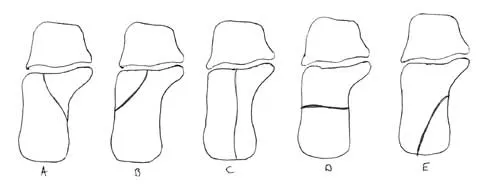

In Figure 14, the primary fracture line in a calcaneal fracture is best depicted by which of the following schematics?

Explanation